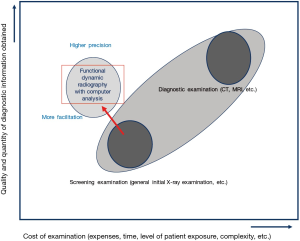

Identifying these techniques as a type of general initial examination (screening examination) using kinetic radiography will allow physicians to obtain more diagnostic data than conventional screening examinations using a method that is far simpler than that used in diagnostic examinations (Figure 7), i.e., these techniques are cost-effective and requires only two times the dose. For example, kinetic and functional data obtained using fDR can provide beneficial diagnostic data that can be used to supplement 3D anatomical data obtained via CT and tissue anatomy data obtained via MRI. Morphological data obtained via X-ray static images are unable to predominate CT 3D data on their own. When performing chest examinations, fDR provides site-specific pulmonary ventilation data that cannot be provided by spirometry, which is the “gold standard” for pulmonary ventilation assessments. Thus, fDR may be an alternative to nuclear medicine, which provides spatial ventilation and blood flow data.